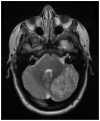

We report the case of a patient with pre-existing multiple sclerosis, who presented with horizontal diplopia, and a prior episode of progressive ataxia and dizziness lasting one week. While initially attributed to multiple sclerosis, subsequent imaging demonstrated a concurrent left cerebellar gangliocytoma, also known as Lhermitte-Duclos disease.